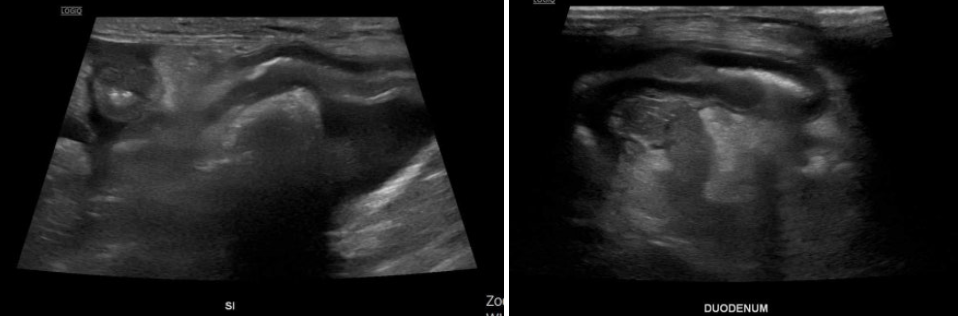

초음파 검사

복부 초음파에서는

- 소장 전반의 점막이 비정상적으로 밝게 보였고,

- 장 점막에 줄무늬 모양의 변화(striation sign)가 반복적으로 관찰되었습니다.

- 장 내에는 액체 저류가 동반되어 있었으며,

- 결장에는 심한 설사 형태의 변이 확인되었습니다.

- 복강 전반에는 중등도의 복수가 존재했고,

- 장 주변 지방 조직에도 염증성 변화가 동반되어 있었습니다.

이러한 소견은 장 점막을 통해 단백질이 지속적으로 소실되고 있는 상태, 즉 단백 소실성 장질환(Protein-losing enteropathy, PLE)을 강하게 시사하는 결과였습니다.

추가로 담낭 내 슬러지와 담낭 및 담도벽의 비후가 확인되었는데, 이는 복수로 인한 부종성 변화와 연관된 소견으로 판단되었습니다.